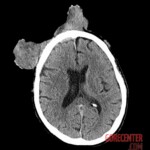

At the hospital, he presented with a large, foul-smelling mass with chronic bleeding, which blocked his right eye and caused significant eyelid swelling. Imaging revealed a malignant mass invading the skull and frontal sinus, along with a separate mass above the right parotid gland. Biopsy confirmed squamous cell carcinoma.

The patient received blood transfusions, stabilizing his condition. Further examinations showed no metastases. Doctors recommended surgical removal of as much of the facial and parotid mass as possible, followed by radiotherapy and immunotherapy. The right eye will likely need to be removed, and the patient will lose function of the right facial nerve, resulting in permanent drooping of the right side of his face.